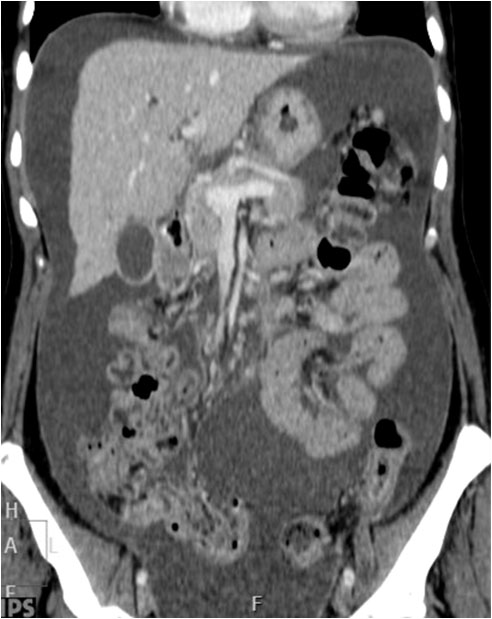

Esta imagen coronal de TC de abdomen nos puede ayudar a entender algunos de los signos de ascitis en la radiografía: el borramiento del ángulo inferior hepático, el ensanchamiento de la banda del flanco o la separación y disposición central de las asas de intestino delgado.

Corte de TC de pelvis con contraste oral e intravenoso que muestra abundante líquido libre abdominal. La presencia del líquido junto a la grasa properitoneal justifican la interfase –marcada con las flechas- en el signo de la cresta ilíaca.

Imagen coronal de TC en otro paciente con ascitis rellenando los recesos pélvicos (flechas) que justifican la imagen de la radiografía.